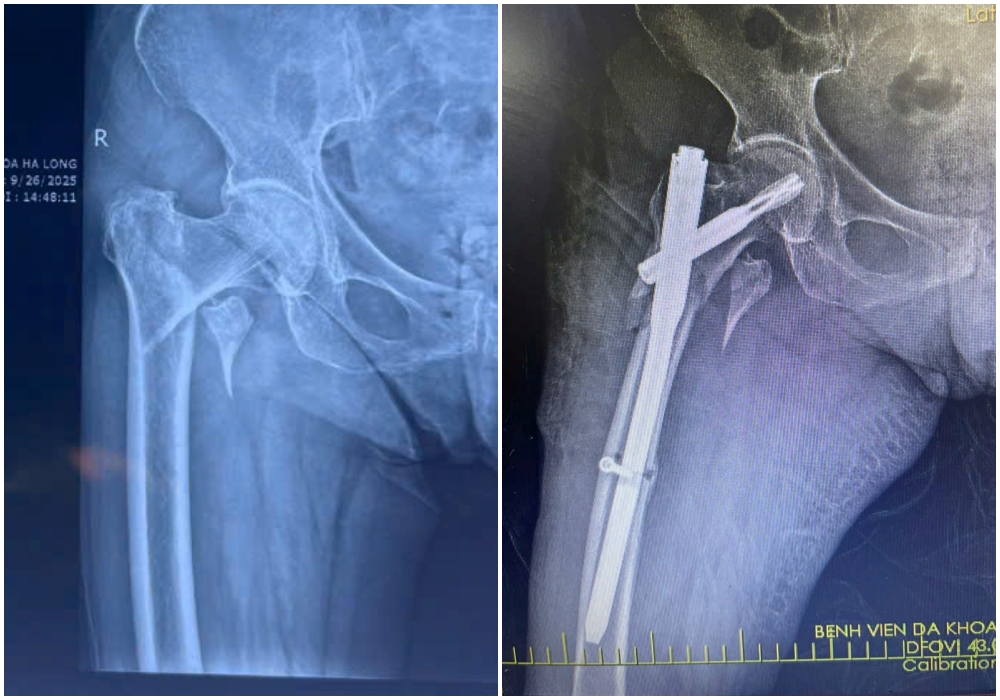

Hình ảnh X-quang gãy liên mấu chuyển xương đùi trái của bệnh nhân H (88 tuổi) được kíp mổ phẫu thuật kết hợp xương ít xâm lấn.

Hình ảnh X-quang gãy liên mấu chuyển xương đùi phải của bệnh nhân N (87 tuổi) được kíp mổ phẫu thuật kết hợp xương ít xâm lấn

Kíp mổ do bác sĩ CKII Loan Tám Bảy, Phó khoa Chấn thương chỉnh hình phụ trách phối hợp cùng các bác sĩ Bệnh viện Đa khoa Hạ Long thực hiện phẫu thuật kết hợp xương gãy liên mấu chuyển xương đùi bằng phương pháp ít xâm lấn. Qua đường rạch da nhỏ khoảng 3-5cm, phẫu thuật viên nắn chỉnh xương gãy về vị trí giải phẫu, sau đó cố định bằng đinh nội tủy PFNA dưới màn hình tăng sáng (C-arm). Ca mổ diễn ra an toàn, thuận lợi trong một giờ. Sau phẫu thuật, cả hai bệnh nhân đều hồi phục tốt, ít đau, có thể ngồi dậy, ăn uống bình thường và đang trong giai đoạn điều trị phục hồi chức năng tích cực.